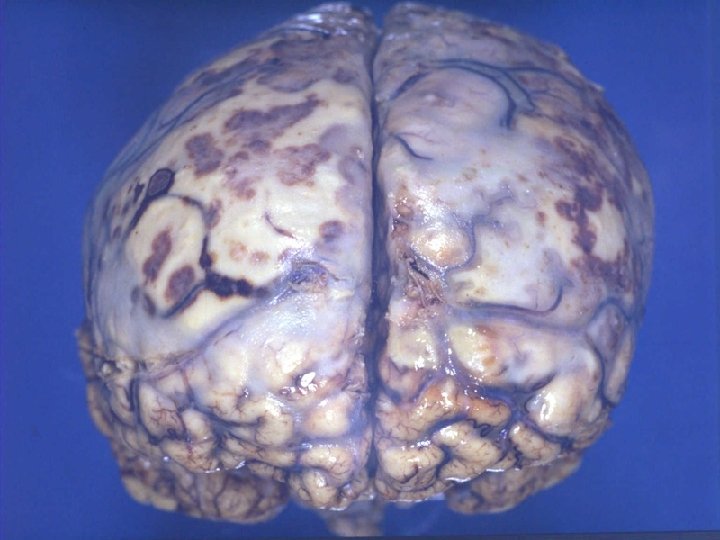

INFECÇÃO: MORTE CELULAR AGUDA E DESTRUIÇÃO TECIDUAL Necrose coagulativa Exemplo clássico deste tipo de processo é a inflamação dos pequenos vasos sanguíneos (vasculite) produzida pela Neisseria meningitidis (meningococcus). Lipopolissacarides na parede da célula bacteriana pode ativar a cascata da coagulação, resultando em trombose. Adicionalmente, as bactérias são levadas pelas células endoteliais para os pequenos vasos que são lesados pelas bactérias conduzindo a trombose local. O resultado final é a necrose do tecido e hemorragia através dos vasos sanguíneos enfraquecidos. Caso ilustrativo: Meningococemia em uma criança.